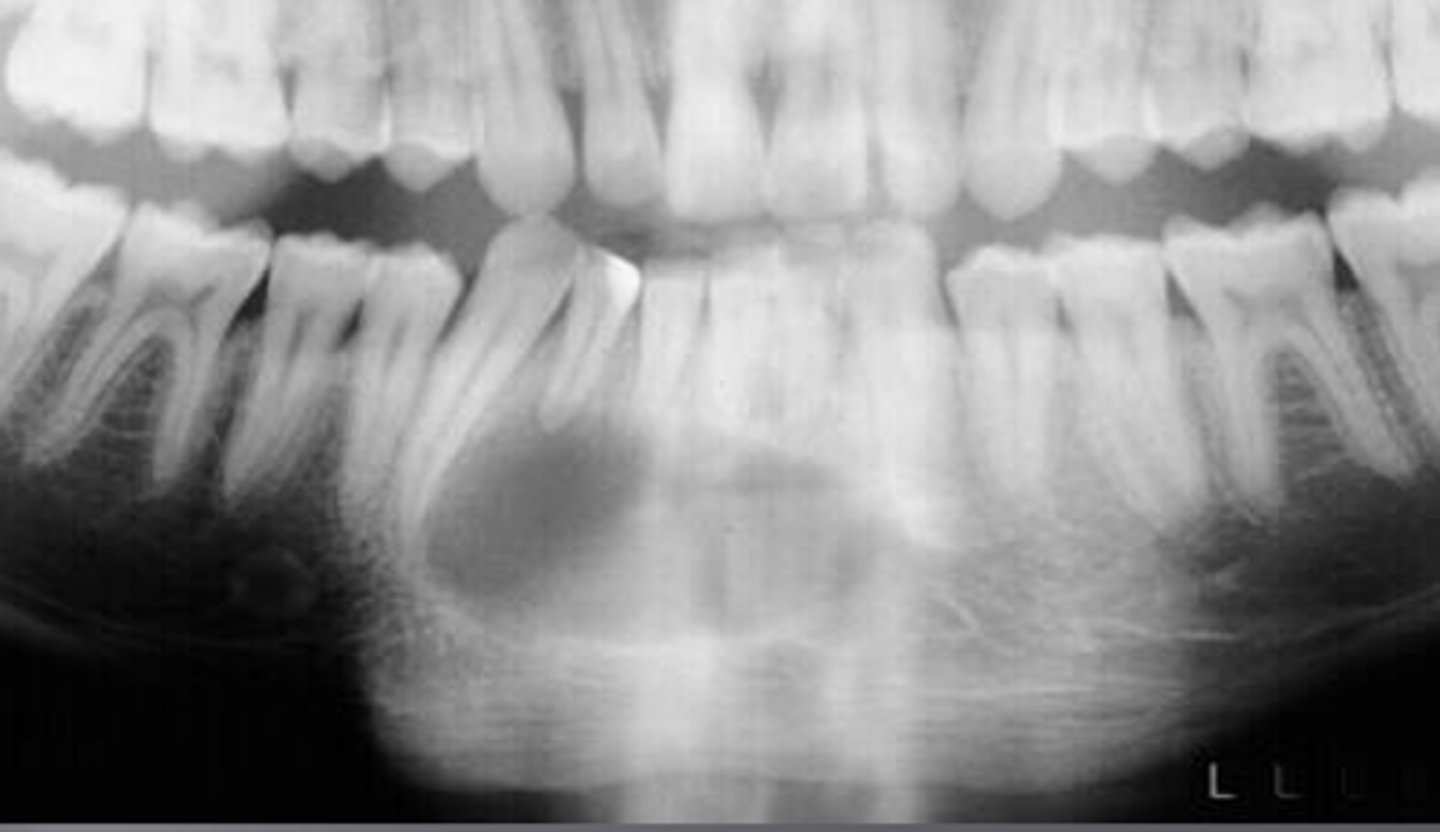

what is this?

what is this radiolucent area in the image?